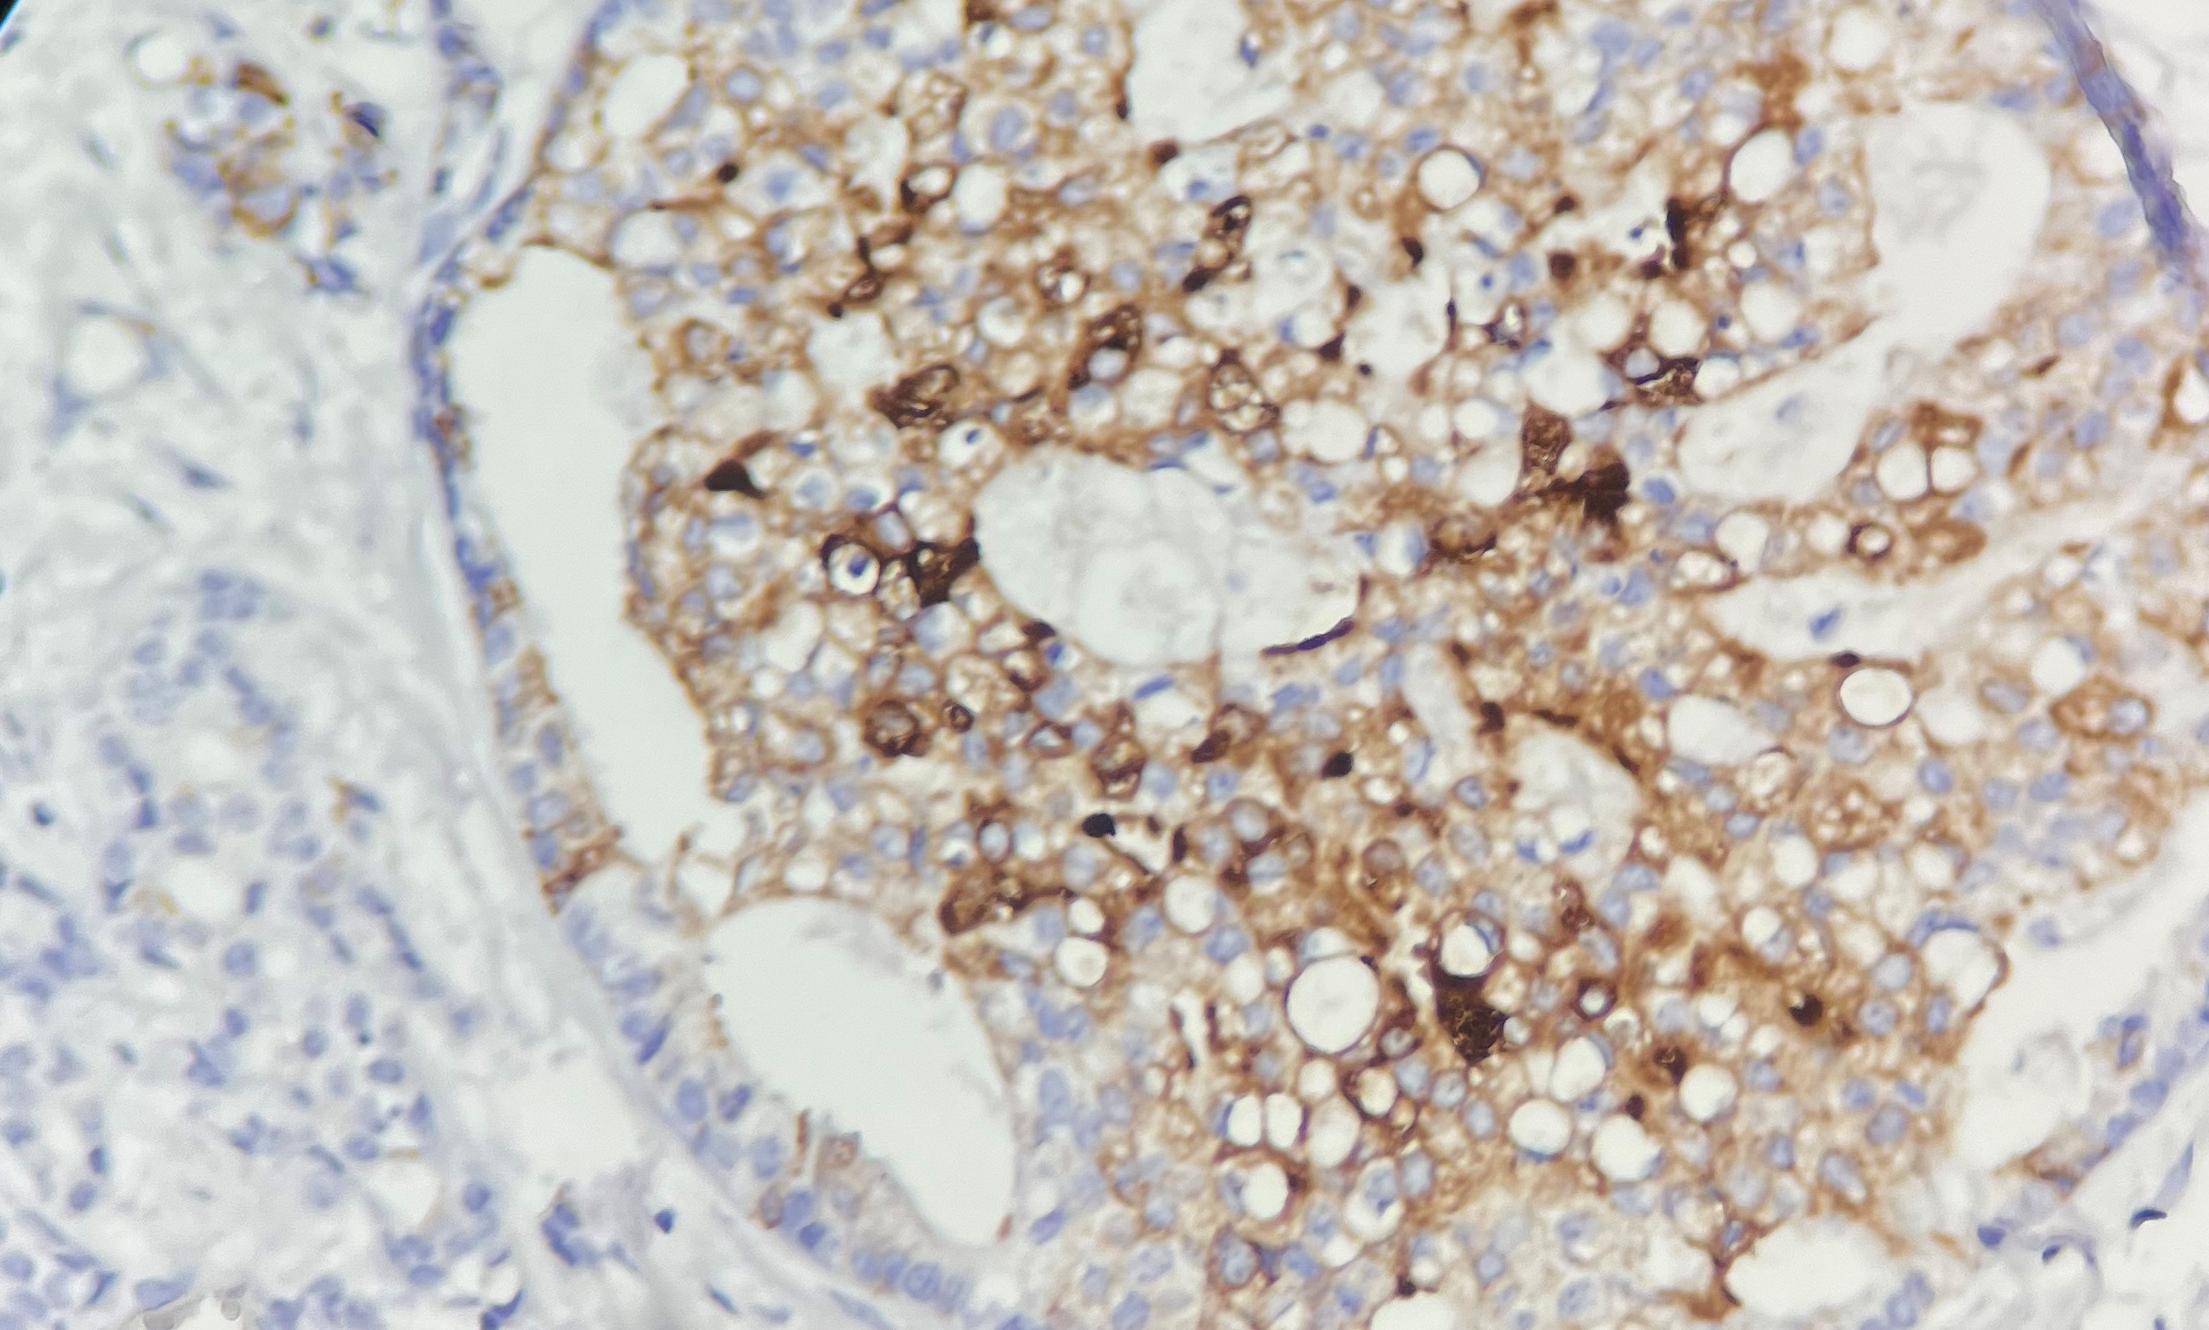

Mammaglobin抗体 是一种特异性识别乳腺特异性10kDa糖蛋白的免疫检测工具,该蛋白在正常组织中仅表达于成人乳腺和汗腺(但汗腺肿瘤中缺失)。作为乳腺癌的高特异性标志物,其价值体现在:①免疫组化检测可识别高达85%的乳腺癌病例;②通过RT-PCR检测外周血循环肿瘤细胞中的mammaglobin mRNA,其表达水平与淋巴结转移等预后因素显著相关。该抗体在乳腺癌诊断、转移监测及预后评估中具有重要临床意义,尤其有助于鉴别乳腺来源的转移性腺癌。